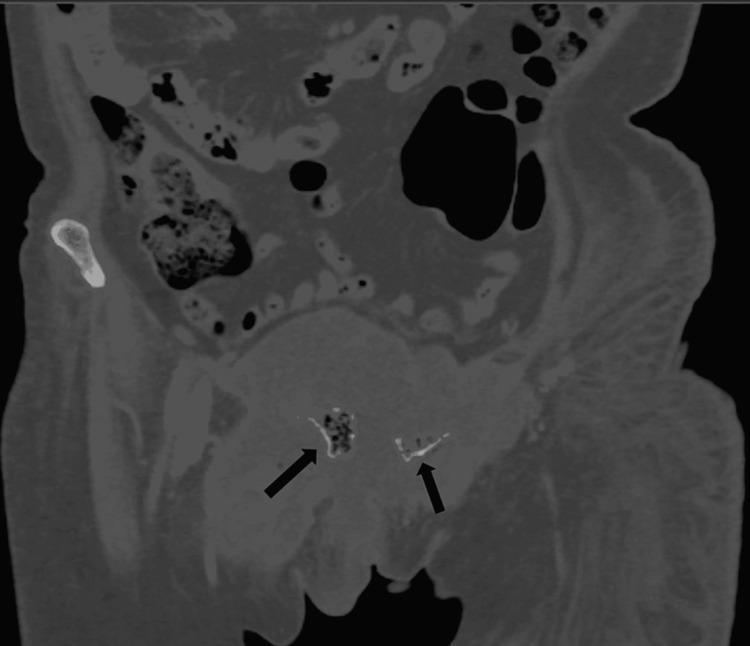

Emphysematous osteomyelitis is an uncommon and fatal disease that can only be confirmed with a contrast-enhanced CT scan showing characteristic features of air locules within the bone. It usually occurs in the setting of existing comorbidities and suppressed immune system resulting in widespread bacteremia which may be mono or poly-microbial. Presented here is a case of this disease caused by an unusual anaerobe affecting the pubic bone. This case emphasizes the importance of early imaging as it is crucial for the diagnosis and can facilitate early aggressive management. Moreover, it highlights the importance of early intravenous antibiotics and surgical intervention, which can be life-saving and result in a better outcome in the future.

气肿性骨髓炎是一种罕见的致命疾病,只有通过增强CT扫描显示骨内有特征性的小气腔才能确诊。它通常发生在存在合并症和免疫系统抑制的情况下,导致广泛的菌血症,可能是单一微生物或多种微生物感染。本文介绍了一例由一种不常见的厌氧菌引起的耻骨气肿性骨髓炎病例。该病例强调了早期影像学检查的重要性,因为它对诊断至关重要,并且有助于早期积极治疗。此外,它突出了早期静脉使用抗生素和手术干预的重要性,这可能挽救生命并在未来带来更好的结果。